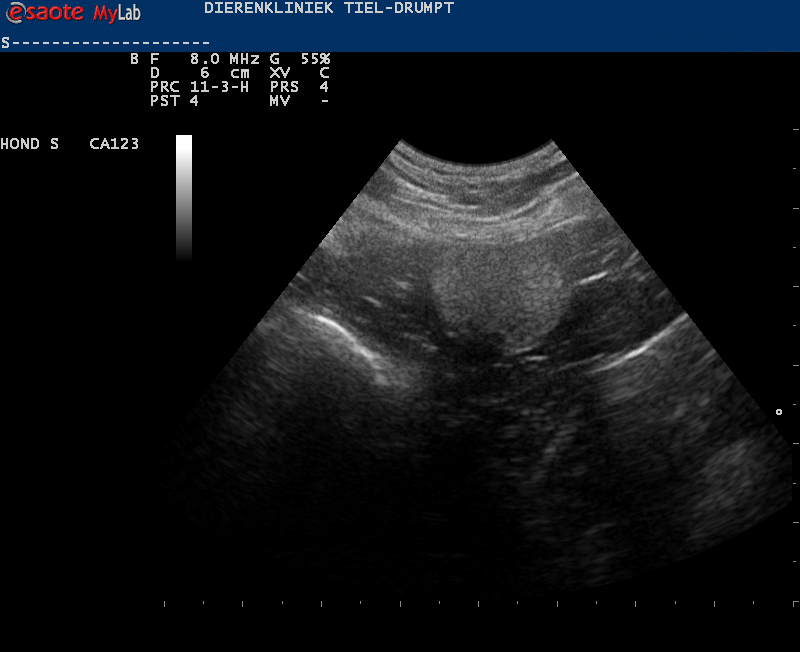

Denk hierbij bijvoorbeeld aan het verwijderen van een binnenbal die in de buik ligt (cryptorche testikel), waarbij er laparoscopisch geassisteerd wordt. Door middel van een echo is er eerst gekeken waar de testikel ligt.